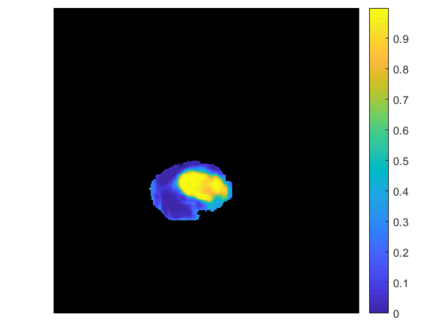

Gliomas are brain tumors composed of different highly heterogeneous histological subregions. Image analysis techniques to identify relevant tumor substructures have high potential for improving patient diagnosis, treatment and prognosis. However, due to the high heterogeneity of gliomas, the segmentation task is currently a major challenge in the field of medical image analysis. In the present work, the database of the Brain Tumor Segmentation (BraTS) Challenge 2018, composed of multimodal MRI scans of gliomas, was studied. A segmentation methodology based on the design and application of convolutional neural networks (CNNs) combined with original post-processing techniques with low computational demand was proposed. The post-processing techniques were the main responsible for the results obtained in the segmentations. The segmented regions were the whole tumor, the tumor core, and the enhancing tumor core, obtaining averaged Dice coefficients equal to 0.8934, 0.8376, and 0.8113, respectively. These results reached the state of the art in glioma segmentation determined by the winners of the challenge.